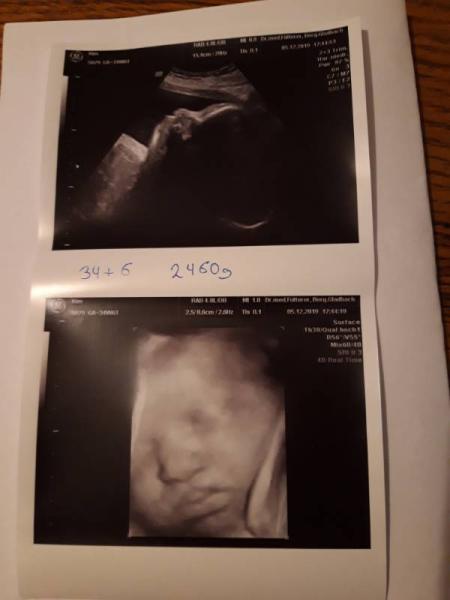

Gestern bei 34+6 waren wir wieder beim Ultraschall Und unsere süße Maus ist zum verlieben Mittlerweile wiegt sie ca. 2460g und entwickelt sich sehr gut. Alles zeitgerecht. Zwischen durch hat sie gelächelt und uns die Zunge rausgestreckt Und dann konnte man sehen wie sie das Fruchtwasser trinkt. Mein Gebärmutterhals ist schon auf 1,8cm verkürzt aber mittlerweile Entwarnung das sie zu früh kommen wird. Mit dem Magnesium haben wir das ganz gut in den Griff bekommen so, dass ich es langsam wieder absetzen soll Ich wünsche euch allen einen schönen Nikolaus Und hier noch ein Bild von ihr

Bild zu Gestern wieder Untersuchung gehabt - Forum für Januar - Mamis

Sehr sehr süßes Foto Wahnsinn das sie einfach schon wie richtige Babys aussehen ! Wir sind dann übrigens gleich weit ! Heute 35 ssw ! Hatte gestern auch einen Termin unsere maus wiegt stolze 2250 gr !

Bild zu